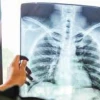

Bartın İl Sağlık Müdürlüğü, tüberküloz (verem) hastalığına karşı vatandaşları uyardı. Yapılan açıklamada, tüberkülozun başta akciğerler olmak üzere solunum yolu ve diğer organları tutabilen bulaşıcı bir enfeksiyon hastalığı olduğu hatırlatıldı.

İl Sağlık Müdürlüğü’nün bilgilendirmesinde, tüberküloz belirtilerinin genel yakınmalar ve akciğere özgü yakınmalar olmak üzere iki grupta değerlendirildiği ifade edildi. Akciğer dışı organ tutulumu durumunda ise tutulan organa özgü belirtilerin görülebileceği belirtildi.

Genel yakınmalar arasında özellikle akşama doğru yükselen ateş, gece terlemesi, kilo kaybı, iştahsızlık ve halsizlik yer alırken; akciğere özgü yakınmaların ise iki-üç haftadan uzun süren öksürük, balgam çıkarma, kan tükürme, göğüs ve sırt ağrısı, nefes darlığı ile ses kısıklığı olduğu bildirildi.